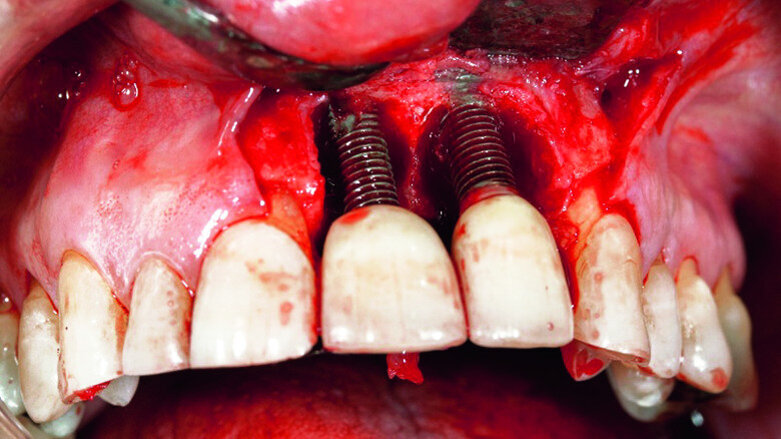

In accordance with the described protocol, a mucoperiosteal flap was created in order to obtain full access to the severe four-wall defect (Fig. 3). The implant surface was mechanically cleaned with diamond-coated burs (Fig. 4). Chemical debridement of the surface with subsequent antibiotic impregnation was performed (Figs. 5 & 6).